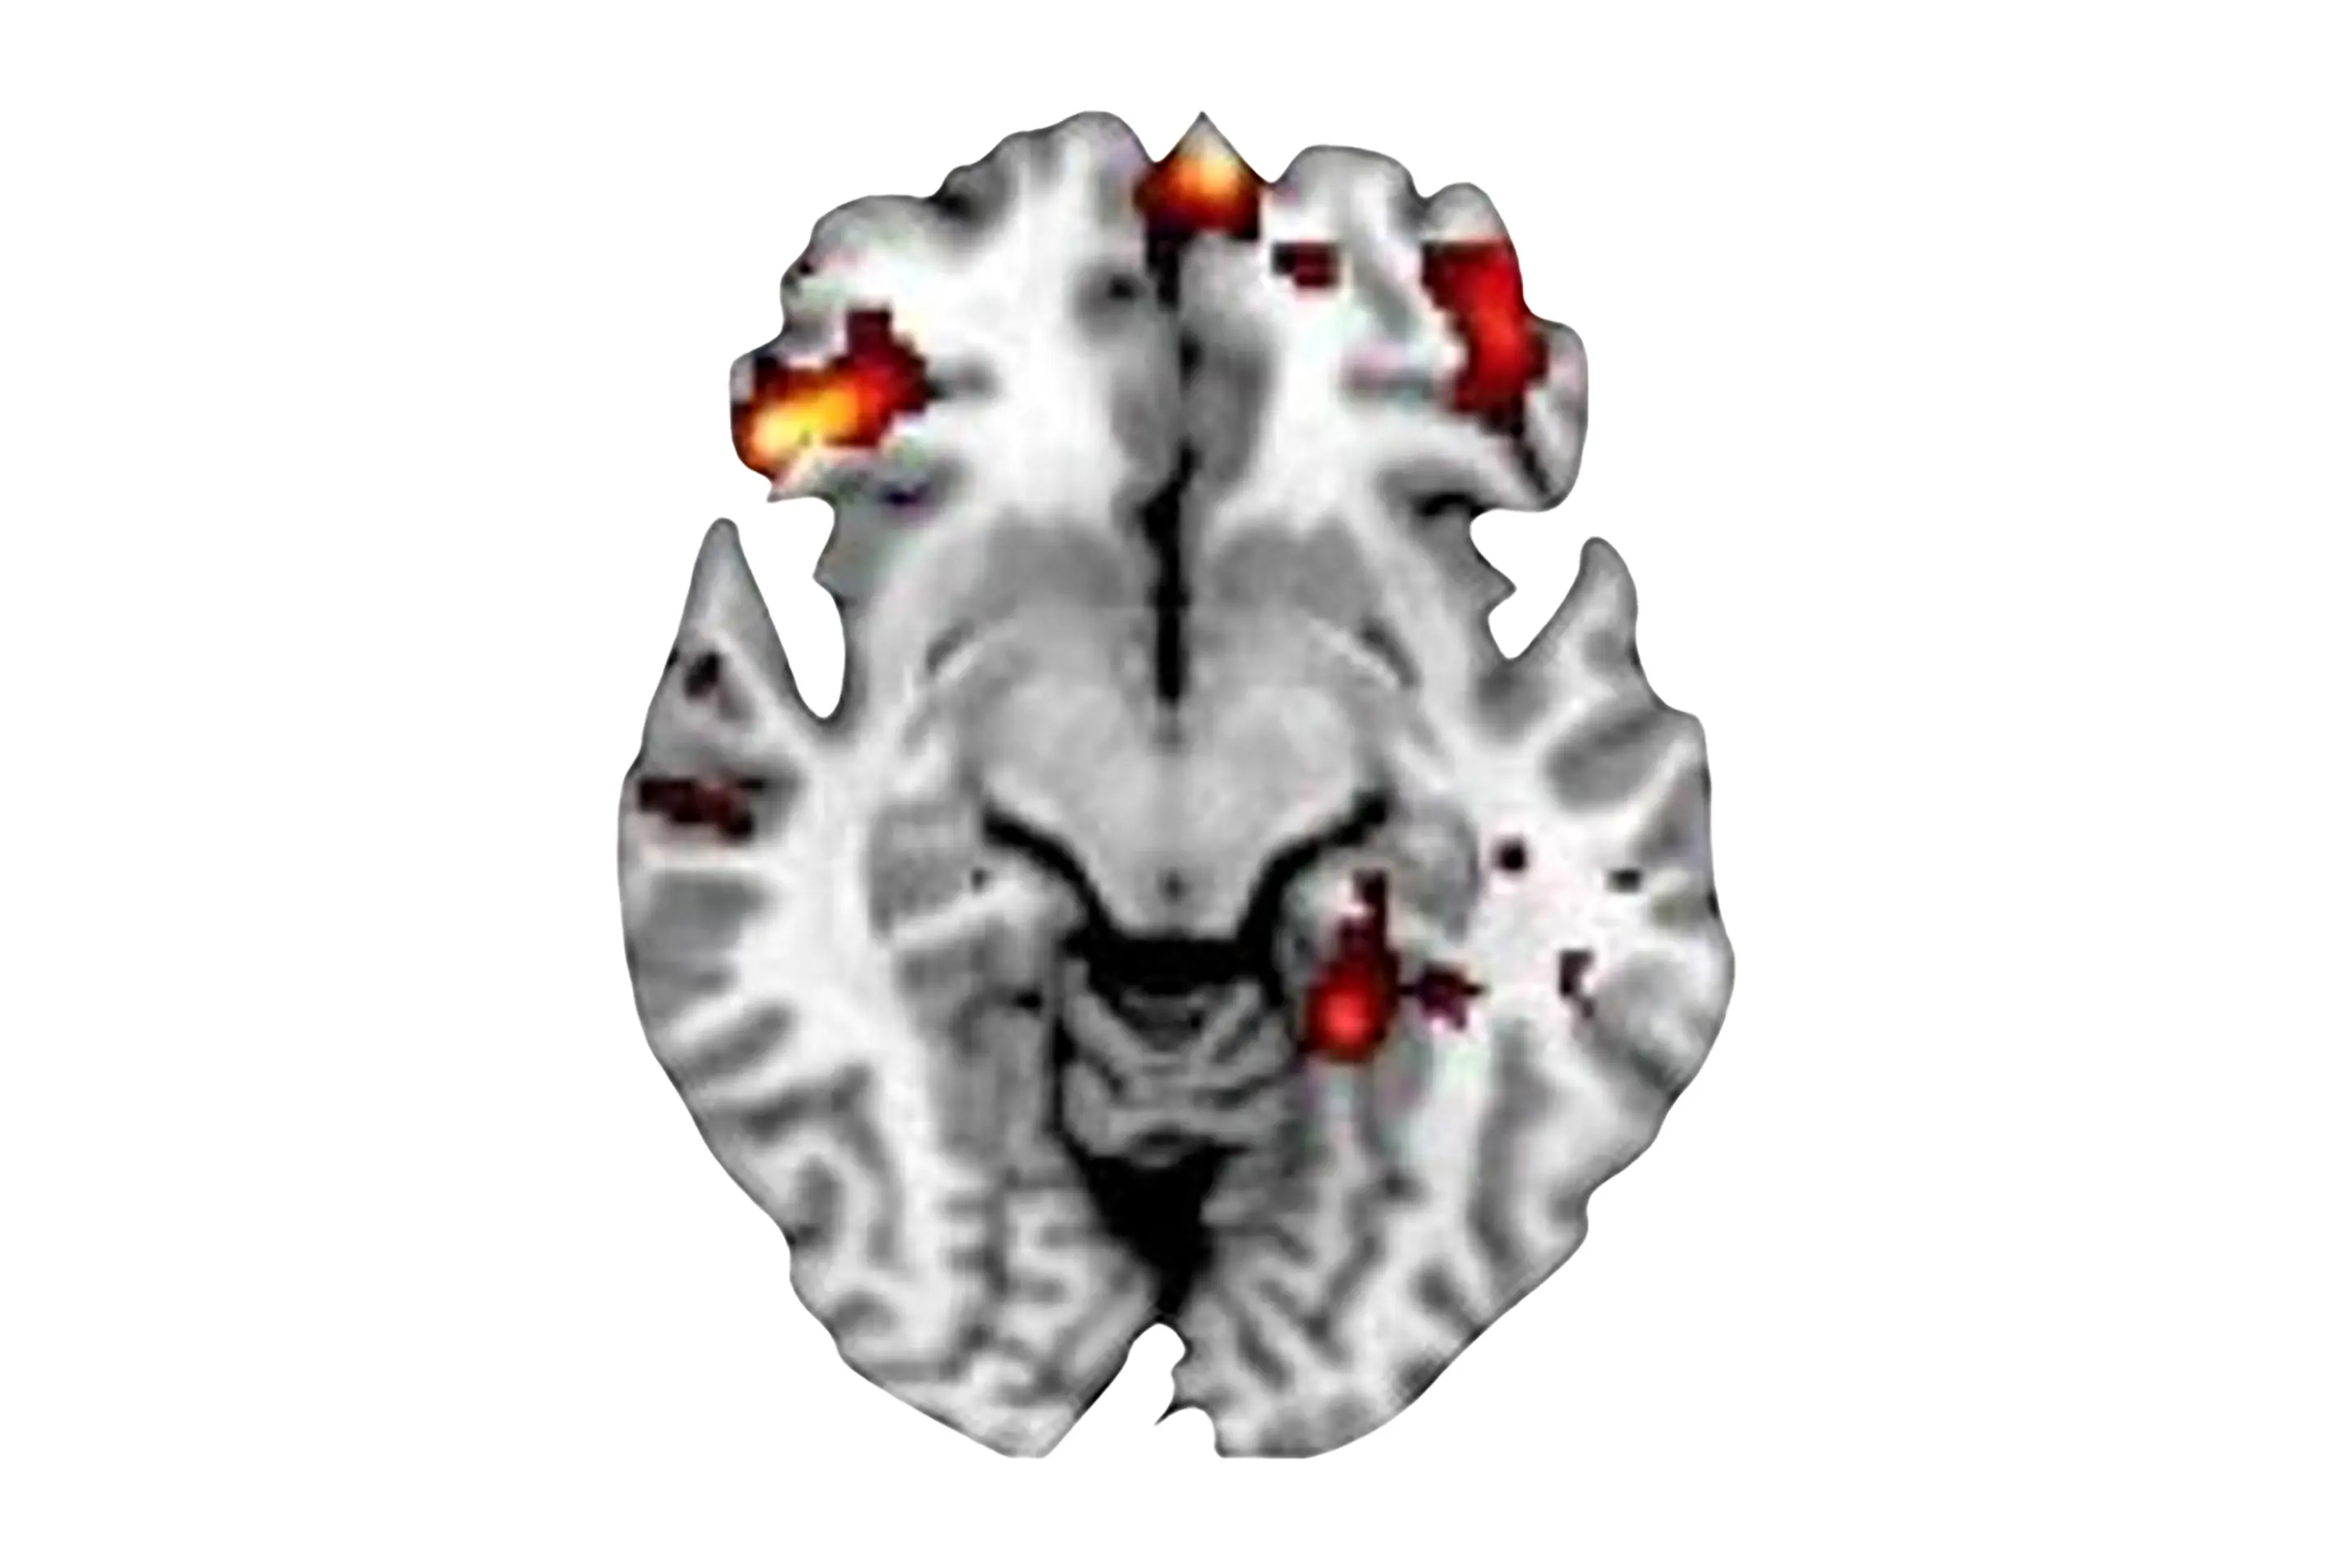

核磁共振扫描显示,与对照组相比,患有强迫症的青少年的大脑活动模式有所不同。眶额皮层(OFC)的差异尤为明显,该区域位于额叶,参与决策和行为控制。

在决策任务中,强迫症参与者的外侧 OFC 表现出低度活跃,而内侧 OFC 则表现出过度活跃。研究人员还发现,过度活跃与强迫症症状的严重程度有关,这支持了决策表现与强迫症之间的联系。